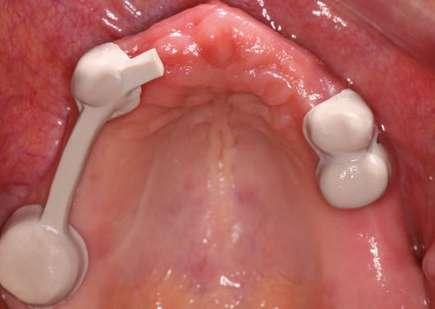

REHABILITACIÓN DE LA ARCADA

SUPERIOR CON UNA PRÓTESIS

REMOVIBLE UTILIZANDO CORONAS TELESCÓPICAS DE ZIRCONIA Y PEEK

El objetivo de este caso clínico es presentar una opción de tratamiento para la rehabilitación de una arcada completa con prótesis removible, retenida por coronas telescópicas de ZrO2 y PEEK, para un paciente sistémicamente comprometido.

Presentación del caso

Paciente femenino de 61 años de edad, acude al Posgrado de Prostodoncia e Implantología de la Universidad de la Salle Bajío remitida por su médico general del Seguro Social para saneamiento y rehabilitación de su condición oral. La paciente es

no fumadora y refiere antecedentes de adenocarcinoma, quimioterapia, osteoporosis y la indicación de administrar bifosfonatos intravenosos. A pesar de sus antecedentes, su médico consideró pertinente realizar su tratamiento dental.

Plan de tratamiento

Basándonos en el examen clínico y radiográfico, se opta por retirar la prótesis fija superior y realizar las extracciones de los dientes fracturados, así como la eliminación de caries y cambio de amalgamas. Se realiza fase de saneamiento eliminando caries y restauraciones defectuosas, dando lugar así a un edentulismo parcial de la arcada superior (Fig. 1a, 1b). Después de efectuar el diagnóstico y anamnesis se decide no colocar implantes y hacer una prótesis removible retenida por coronas telescópicas friccionales.

Tratamiento

Se comienza el caso elaborando un enfilado dental a manera de maqueta para llevar a cabo la evaluación de la futura dimensión vertical planificada y con ello, el desgaste a realizar para que los órganos dentales reciban las coronas primarias que serán elaboradas en ZrO2 (Prettau® 2 Dispersive®, Zirkonzahn Worldwide). Las preparaciones de las coronas prima-

ras nos proporcionaban 1 mm de espacio protésico para poder otorgarles el grosor necesario y así evitar la posibilidad de algún daño biológico (Fig. 2a). Una vez realizadas las preparaciones, se procede a tomar impresión fisiológica con técnica de doble hilo a un tiempo, con material de polivinilsiloxano (Virtual, Ivoclar Vivadent) (Fig. 2b).

Después de preparar los modelos fisiológicos en los que se realizará el trabajo final, se procedió a la toma de registros intermaxilares para obtener la relación céntrica, utilizando una base de acrílico y los registros de cera, logrando determinar de esta manera la dimensión vertical deseada (Fig. 2c).

Fase técnica

Se envía el modelo de trabajo articulado al laboratorio, se diseñan y elaboran las coronas primaras de ZrO2 con una angulación en sus paredes de 4 grados con el fin de obtener, no solo una buena retención, sino también una buena pasividad.

Las coronas secundarias que irán dentro de la prótesis removible fueron fabricadas con PEEK (Tecno Med, Zirkonzahn Worldwide) (Fig. 2d).

Se realizó la prueba de éstas intraoralmente para confirmar la pasividad y se observa, que no solo se logró una buena pasividad, sino también una excelente integración a los tejidos blandos (Fig. 3a y 3b).

Se enviaron de nuevo las coronas al laboratorio para elaborar la dentadura en Cromo Cobalto donde se confeccionó un rodillo de cera para realizar el enfilado de los dientes anteriores (Neo.lign®, Bredent) (Fig. 3c).

Terminado el enfilado y después de una última prueba en cera, se envía el trabajo al laboratorio para procesar la estructura final, la cual se fabrica en acrílico de alto impacto y se pule al alto brillo (IvoBase System, Ivoclar Vivadent) (Fig. 3d).

Se cementan las coronas primarias siguiendo el concepto APC(8) y se coloca la prótesis a la paciente obteniendo excelente retención y pasividad. Se ajusta la oclusión y se le indican las técnicas de higiene y mantenimiento de la prótesis (Fig. 4a).